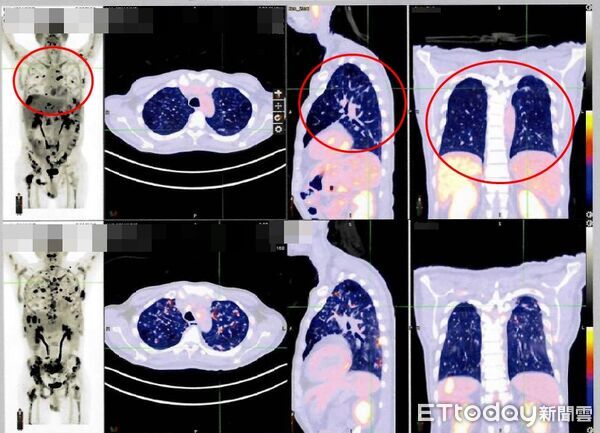

▲從病人接受免疫細胞治療後的影像資料(紅圈處),可發現癌細胞明顯減少。(圖/雙和醫院提供)

一名約50歲的第4期肺癌患者,歷經多次化療與標靶治療,為尋求更多機會,去年從香港來台尋求新治療選項,經評估後接受免疫細胞整合療程,半年後除影像顯示病情穩定,長期困擾的疼痛也明顯緩解,體能、生活品質均有改善。